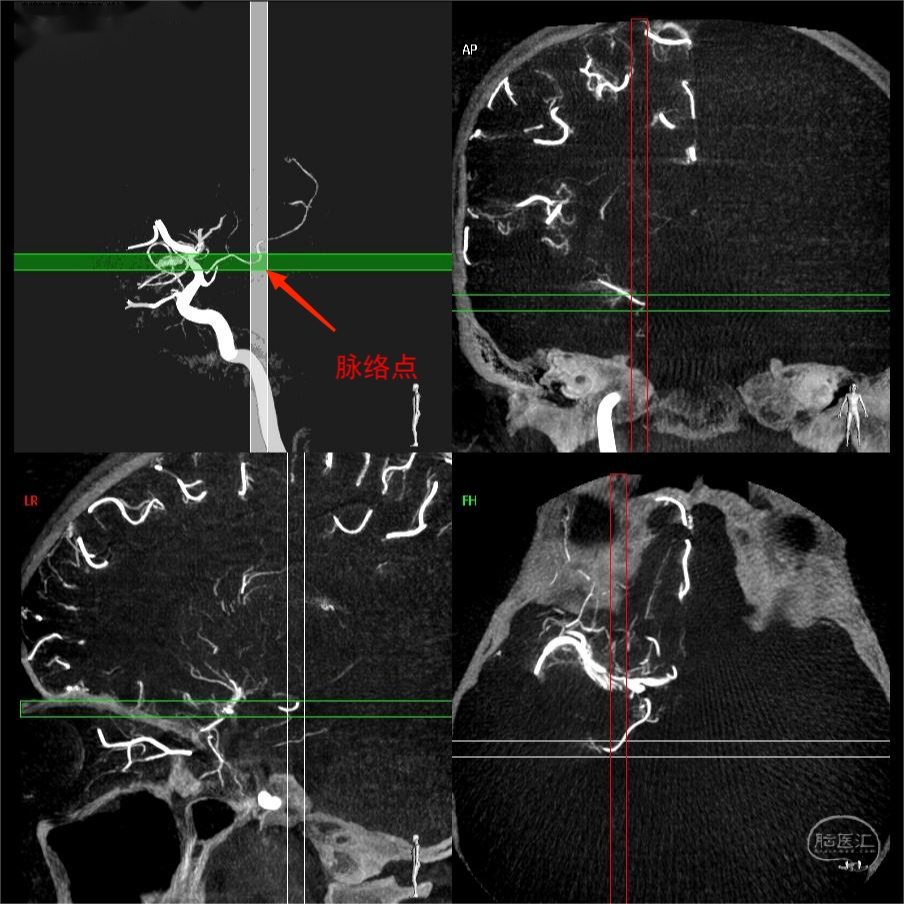

图13 同一例患者右侧颈内动脉3D成像(图中为侧位),经过Xper CT冠状位、矢状位及轴位MIP图像证实脉络点的位置。